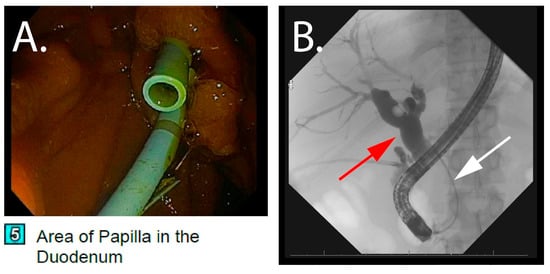

2.3. Index Hospitalization